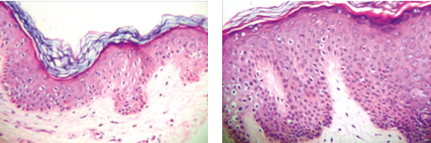

These treatments are designed to increase the thickness of the epithelium as shown on the right when compared to the thinning surface of the image on the left.

CO2 laser therapy to the vagina has been found to be highly effect in helping to reverse the effects of genitourinary syndrome. It is a painless procedure. While, these procedures were initially developed for normal women for “vaginal rejuvenation," the effects have found to be exactly what is needed for women suffering from genitourinary syndrome or vaginal atrophy. The laser results in improve collagen production and blood supply to the vagina resulting in better lubrication, resolution of pain with intercourse and better sensation.

RF therapy to the vagina has been found to be highly effect in helping to reverse the effects of genitourinary syndrome. While, these procedures were initially developed for normal women for “vaginal rejuvenation," the effects have found to be exactly what is needed for women suffering from genitourinary syndrome or vaginal atrophy. The RF therapy results in improve collagen production and blood supply to the vagina resulting in better lubrication, resolution of pain with intercourse and better sensation. New studies have shown growth of nerve fibers following Thermiva.